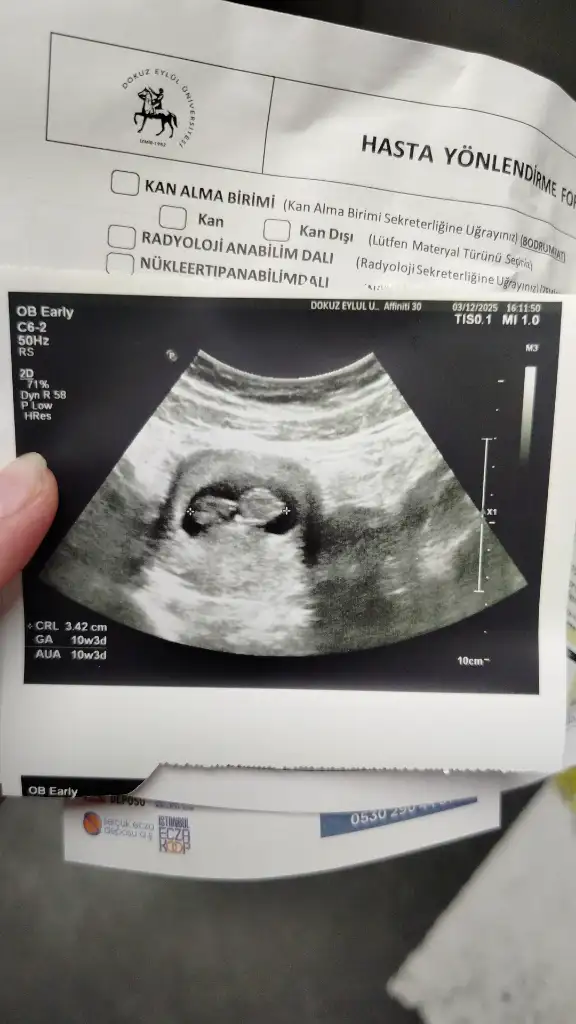

Kabızlık sorunu bende var 18. hafta itibariyle bu süre artabilir dedi doktorum, bana activa shot ve kefir önerdi birde lifli gıdaları artır dedi elma havuç yulaf ceviz dedi sende bir dene istersen ben activa shotlardan biraz rahatladddım gibiKızlar günaydın bizde 13+ 4 de perinatoloji dr detaylı renkli ultrasona gittik. 1 saate yakın sürdü. Her yer detaylı ölçülerek incelenerek rapor hazırlandı .Şükür her şey yolunda.

Eki Görüntüle 3675353

ANNE ADI YAŞ KAÇINCI ÇOCUK SAT KESE KALP ATIŞI CİNSİYET TAHMİNİ DOĞUM TARİHİ BEBEĞİN İSMİ kedikulagi 28 1 25 AĞUSTOS 4+2 6+2 01 HAZİRAN @afitap06 27 1 25 AĞUSTOS 5+3 7+2 01 HAZİRAN @birisii16 26 2 25 AĞSUTOS 5+0 7+0 01 HAZİRAN @Melodya 34 1 26 AĞUSTOS 6+3 6+3 02 HAZİRAN @Tugceir 24 1 27 AĞUSTOS 8+2 8+2 03 HAZİRAN @xxperia 27 29 AĞUSTOS 5+3 6+2 05 HAZİRAN @Efnanala3494 31 1 30 AĞUSTOS 5+5 7+3 06 HAZİRAN @Biamu 35 2 31 AĞUSTOS 6+2 7+2 07 HAZİRAN @merveyks 31 1 1 EYLÜL 5+3 7+0 8 HAZİRAN @berfinAk 23 3 1 EYLÜL 4+3 5+4 6 HAZİRAN @eppursi 26 1 2 EYLÜL 5+4 7+2 8 HAZİRAN @sadeozgurlesme 37 2 2 EYLÜL 10+0 12+0 9 HAZİRAN @eliifzgen 27 1 3 EYLÜL 5+3 7+2 10 HAZİRAN Aslan @gulaysedeniz 36 1 5 EYLÜL 7+0 7+0 12 HAZİRAN @muczm 31 2 5 EYLÜL 5+4 6+5 12 HAZİRAN @Phila 33 1 6 EYLÜL 5+2 7+2 13 HAZİRAN @bestinfo 33 1 7 EYLÜL 4+4 6+4 14 HAZİRAN @munisem 39 1 7 EYLÜL 5+1 7+1 14 HAZİRAN @Manolya_31 44 2 8 EYLÜL 6+0 6+2 15 HAZİRAN @Melika88 37 2 8 EYLÜL 5+5 @mlk230923 23 1 8 EYLÜL 5+3 7+5 19 HAZİRAN @Mervo680 27 1 9 EYLÜL 4+2 7+1 16 HAZİRAN M muhasebeci2547 27 1 10 EYLÜL 6+3 6+3 17 HAZİRAN @kittenlyy 34 2 10 EYLÜL 5+0 6+5 17 HAZİRAN @sedcyl 31 2 10 EYLÜL 5+5 7+4 18 HAZİRAN @yarenCu 34 3 10 EYLÜL 5+2 6+1 18 HAZİRAN @demre123 30 1 11 EYLÜL 6+1 6+1 19 HAZİRAN @blackbird87 38 3 11 EYLÜL 5+5 6+4 19 HAZİRAN @Uyelogg 35 2 12 EYLÜL 5+0 7+2 20 HAZİRAN @nurmus87 38 1 12 EYLÜL 5+0 7+0 21 HAZİRAN @kelebek922 32 2 13 EYLÜL 7+0 @MELIKE5758 26 1 14 EYLÜL 5+4 6+4 22 HAZİRAN @damybe 35 1 ve 2 4 EKİM TRNSFR 5+4 6+1 22 HAZİRAN @Kittylovers 44 3 ve 4 4 EKİM TRNSFR 5+3 6+1 22 HAZİRAN @tomrisuyar 35 1 ve 2 4 EKİM TRNSFR 5+4 6+3 22 HAZİRAN @Paradisee 30 1 6 EKİM TRNSFR 5+2 6+2 24 HAZİRAN @Esmeren 32 1 17 EYLÜL 4+5 6+2 25 HAZİRAN @dmldgn 26 1 18 EYLÜL 26 HAZİRAN @zingarina10 34 5+3 @MisirUnluPogaca 43 1 19 EYLÜL 5+3 6+4 27 HAZİRAN @bfbf 27 1 19 EYLÜL 5+3 7+3 26 HAZİRAN S simaykk123 34 2 19 EYLÜL 4+1 6+6 26 HAZİRAN @cancaney 37 1 19 EYLÜL 6+1 8+3 26 HAZİRAN @asluh 26 1 ve 2 20 EYLÜL 5+0 6+4 28 HAZİRAN P Prettywomaan 25 2 20 EYLÜL 4+4 7+2 28 HAZİRAN @zyynppp 26 1 21 EYLÜL 29 HAZİRAN @yolculuk2345 28 1 22 EYLÜL 6+0 6+0 30 HAZİRAN @blimundacbn 39 2 22 EYLÜL 5+1 30 HAZİRAN @adsuma 23 1 24 EYLÜL 5+0 6+6 @Sedagl_ 30 1 24 EYLÜL 5+2 7+0 1 TEMMUZ B binefes 28 1 25 EYLÜL 6+5 6+5 2 TEMMUZ